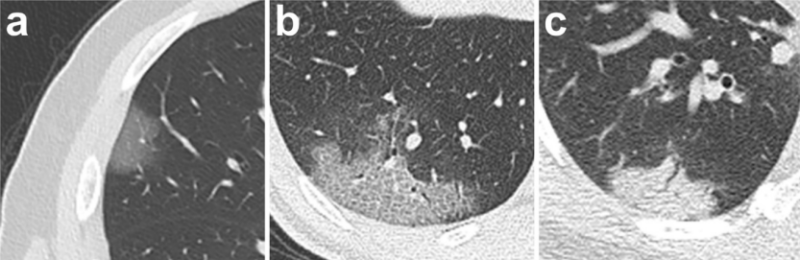

+ Thương tổn thường cả hai bên, nhiều ổ là thường gặp, phân bố thường ở ngoại vi, dưới màng phổi và đáy phổi (hình 1, 2) [1,2,5,6]. Theo một thống kê trên 51 bệnh nhân [7] thì thương tổn hiện diện ở cả hai bên phổi trong 88% trường hợp trong đó thương tổn tác động trên nhiều hơn 2 phân thùy , 85% thương tổn ở ngoại vi và 82% trường hợp thì thương tổn thuộc các phân thùy sau.

+ Hầu hết các báo cáo cho thấy thương tổn thể hiện bởi hình ảnh đám mờ với các hình thái: từ dạng kính đục đơn thuần (hình 1a)-loại này là nổi trội trong giai đoạn sớm, đến đám mờ dạng kính đục có biểu hiện dày vách liên tiểu thùy, vách trong tiểu thùy, dày dạng lưới (hình 1b), đến đám mờ dạng kính đục kèm đặc phổi từng phần (hình 2A); đám mờ dạng đặc phổi đơn thuần (hình 1c). Đám mờ thường có hình dạng hình học; có một số trường hợp thì các đám mờ dạng kính đục hay đám mờ đặc phổi lại có dạng hình tròn hoặc có biểu hiện dấu halo đảo ngược (dấu hiệu để chỉ thương tổn gồm viền đặc phổi dày tối thiểu 2 mm bao quanh vùng kính mờ ở trung tâm). Một kiểu thương tổn khác là dải mờ gặp với tần suất ít hơn (bảng 1).

+ Ngoài ra còn có một các dấu hiệu khác như: lớn ra của cấu trúc mạch máu bên trong đám mờ thương tổn (hình 2B), dày vách liên tiểu thùy và trong tiểu thùy tạo nên hình ảnh lát đá không đều (hình 1b, 2A), hình cây phế quản khí (hình 2A), dấu halo đảo ngược.